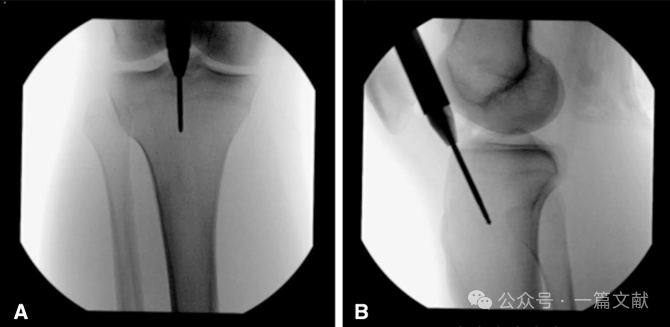

图2,进针点的调整(双针技术):如果第一根针的位置不佳,可以将其保留作为参考,并适当的旋转套筒置入一根新导针,直到获得满意的进针点。在本例中,初始导针偏内侧,因此在外侧置入了一根新导针,使其在正位(AP)上刚好位于外侧胫骨髁间棘的内侧,同时在矢状面上保持相同的位置。这种方法有助于确保髓内钉的准确定位,从而提高手术的精确性和安全性。

图3,术中透视标准正位片,有利于准确评价进针点,此时胫骨外侧缘平分腓骨头,如下图: